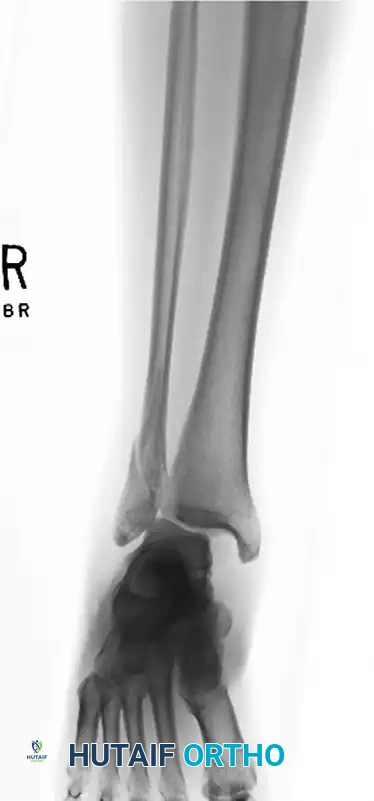

FIGURE 54-7 A: Preoperative lateral malleolar fracture with associated medial clear space widening and severe syndesmotic disruption.